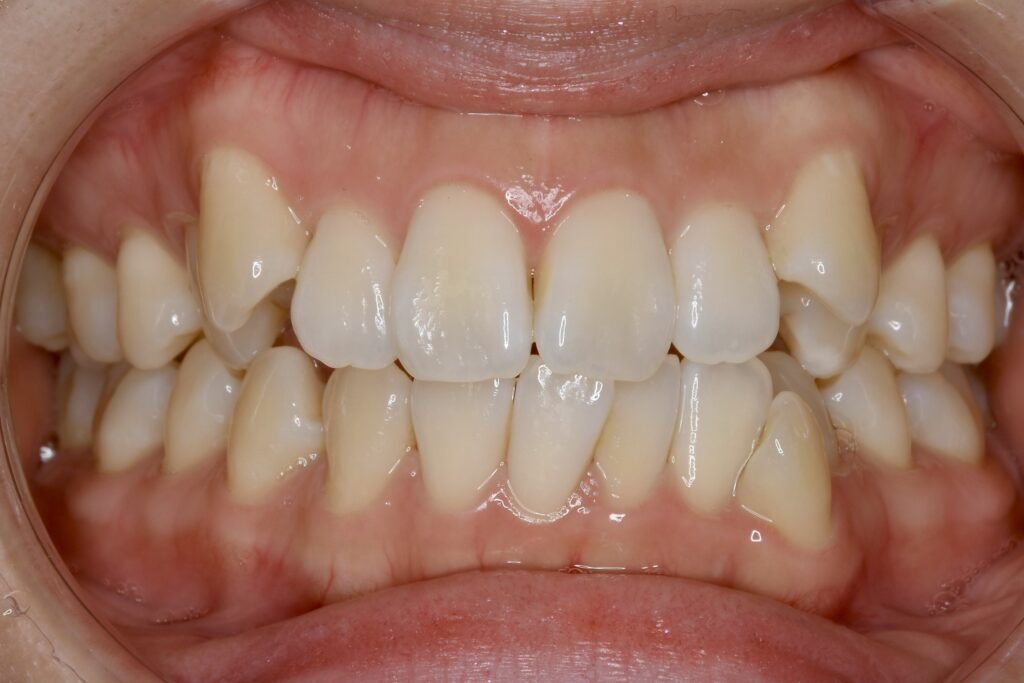

| 主訴 | 上も下も歯並びがガタガタしているので治したい。 |

|---|---|

| 診断名・主な症状 | 叢生 |

| 年齢 | 18歳 |

| 治療内容 | 上下とも歯並びの横幅を広げながら、でこぼこを解消しました。 |

| 使用装置 | マウスピース矯正装置(インビザライン) |

| 抜歯部位 | 抜歯なし |

| 治療期間 | 1年4ヶ月 |

| 通院回数 | 10回 |

| 費用 |

86万円程度(税別) 33990 |

| リスク・副作用 | 痛み、歯肉退縮、歯根吸収、抜歯に伴う出血や腫れが生じることがあります。 |